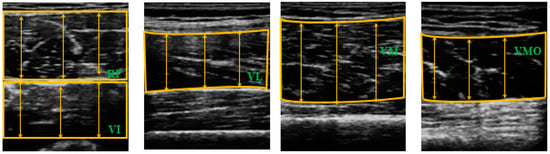

A cross-sectional research design was used to compare quadricep thickness between the RCL and HL before and after ACLR. Quadricep thickness was measured an hour before and 48–72 h after the reconstruction by using a portable ultrasound device (7.5 MHZ transducer, Healcerion, Seoul, Korea). Previous investigations reported excellent intra-rater (ICCs 0.95–0.97) and acceptable-good inter-rater (ICCs 0.62–0.90) reliability of quadriceps thickness measurement using ultrasound [28,29]. To measure the thickness of each quadricep component, the patients were positioned supine and hip external rotation prevented. The thickness of each quadricep component was measured in a random order. The location of the measurement site of each component was based on a previous study [30] (Figure 2). Specifically, the measurements were made along with the length of the thigh from the superior pole of the patella to the anterior superior iliac spine (ASIS). The RF and VI were measured at 50% of the length between the superior pole of the patella and the ASIS [30]. The VL was measured laterally, at 10% of patient’s thigh circumference from the RF and VI measurement sites. The VM was measured medially, at 12.5% of the patient’s thigh circumference from 20% of the length the line between the superior pole of the patella and the ASIS. The VMO was measured 4 cm superior and 3 cm medial from the border of the patella [31]. The image was adjusted until the muscle boundary was visible on the screen and the depth of the image was measured when the femur was centered on the screen. The ultrasound images were recorded three times per muscle by a single examiner. Once all the muscle thicknesses were measured, the images were saved for further analysis.

ImageJ software (National Institutes of health, Bethesda, MD, USA) was used to analyze each muscle thickness. The images were recorded when the boundaries of the muscles were clear and the femur was visible from the center of the screen. The subcutaneous adipose tissue and bone tissue were identified, and the distance between them was defined as muscle thickness [32]. The RF thickness was defined as the distance between the superficial border of the muscle and the deep border of the muscle. The VI thickness was defined as the distance between the superficial border of the muscle and the superficial border of the femur. The VL, VM, and VMO thicknesses were defined as the distances between the superficial and inferior borders of the muscles [31] (Figure 3). Muscle thickness was defined as the average value of three lines placed equally spaced in the muscle belly; the three lines were measured three times each and the average value obtained (Figure 3). The average value of the three images was utilized in the statistical analyses.

Figure 3. The images used to measure the muscle thicknesses of the components of the quadriceps.